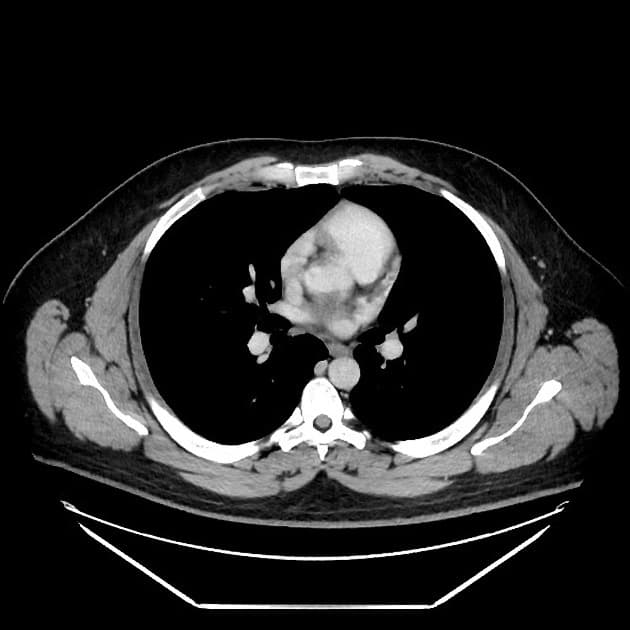

Chụp X-quang bụng không chuẩn bị (CT scanogram) cho thấy hình tăng tỷ trọng (metallic density) tại nửa bụng phải, cụ thể là ống nội soi dạng viên nang bị kẹt (trapped capsule endoscope). Hình ảnh này được xác nhận nằm trong lòng ruột (intraluminal), trong một quai hồi tràng.

Hình ảnh tăng quang (hyperenhancement) và thành ruột non dày lên tại nửa bụng phải, cũng như tại đại tràng trực – xích-ma.

Có các đoạn hẹp (strictures) tại hồi tràng cuối và nhiều đường rò ruột – ruột (entero-enteric) và ruột – đại tràng (entero-colonic) tại hố chậu phải.

Có hiện tượng giãn đoạn trước hẹp (prestenotic dilatation) hồi tràng và đại tràng trực – xích-ma, mức độ thay đổi.